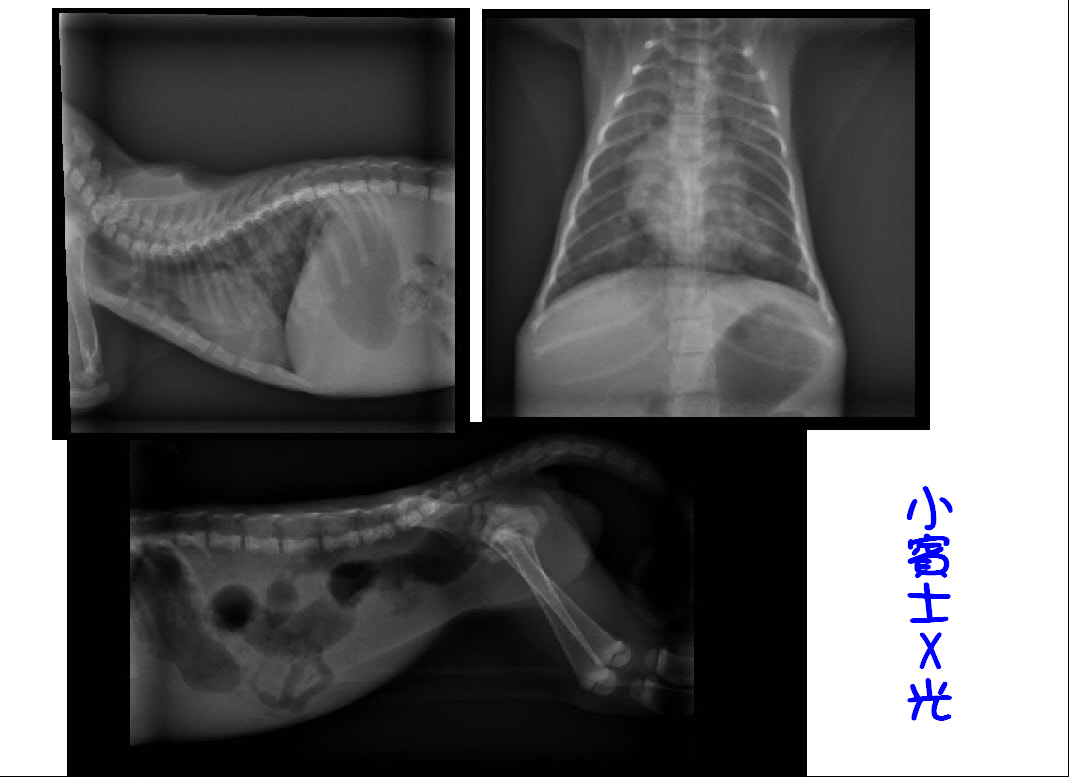

- 編號: 1829

主題: 尿不出來的小賓士 申請者姓名: 陳露露 花色: 申請日期: 2013-01-18 12:10:19 申請者部落格: 申請者臉書網址: 所在縣市/合作醫院: 高雄市/恩澤動物醫院 治療費用: 7490元 需求人數: 16人 已結案 (2013-08-06 14:27:06) 報名人員: Amy(已付款)、施栯萑(已付款)、游淑玲(已付款)、Cinder Gaow(已付款)、Katty Huang(已付款)、麵貓匪(已付款)、廖小喜、Verna Chang(已付款)、Mia Wei(已付款)、Hsin-Wen(已付款)、Wei Lin(已付款)、李脆脆(已付款)、Lynn Lin(已付款)、Lynn Lin(已付款)、黃小吟(已付款)、41(已付款)、招招(已付款)、 候補人員: mavis、 動物病情說明: 小賓士,

在醫生細心的檢查下發現,

小賓士尿道嚴重發炎,

導致尿道口閉鎖,尿液無法排出

故緊急尿道造口手術...

2. X-ray 400